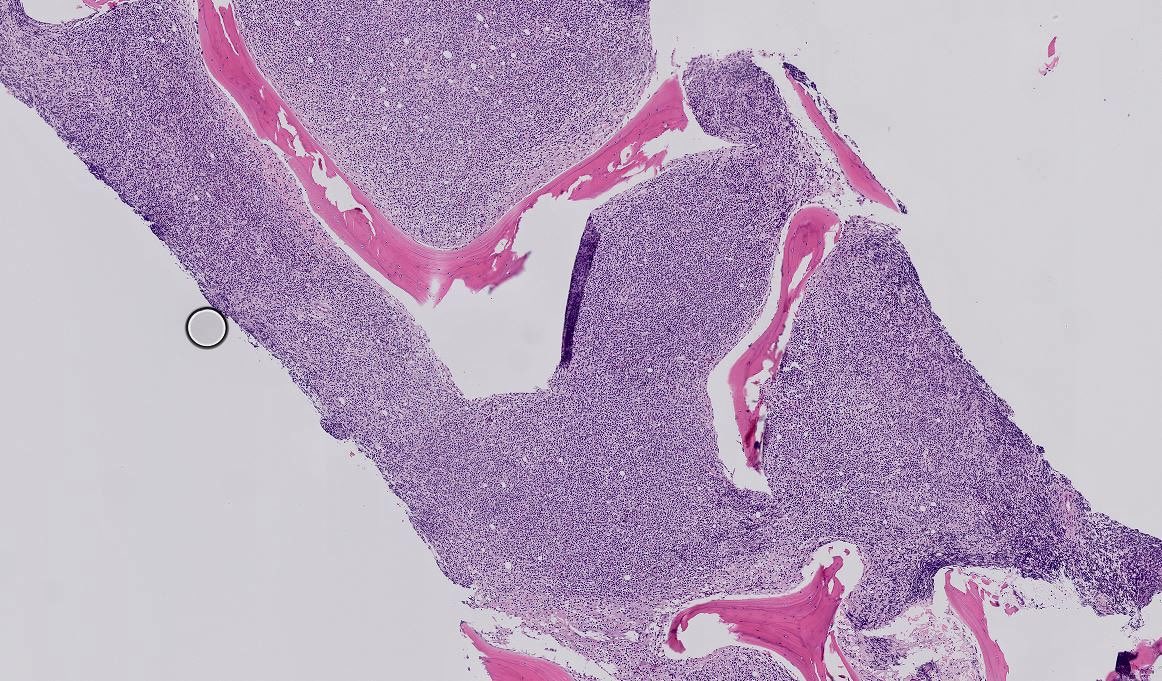

BMB 41 yo male. All these cells are positive for CD3, CD5, CD2, CD7. In the pics you can see the CD4 and CD8. What is your diagnosis? What other stains would you like to see?

Tiger_heme's tweet image. BMB 41 yo male. All these cells are positive for CD3, CD5, CD2, CD7. In the pics you can see the CD4 and CD8. What is your diagnosis? What other stains would you like to see?